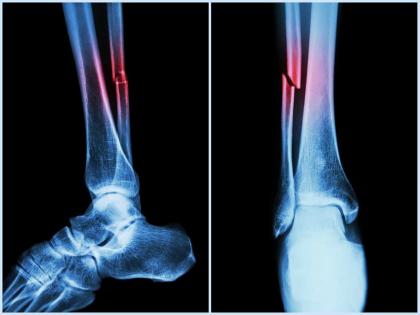

In the study, mice who had Covid-19 showed significant bone loss. This loss decreased the bone mechanical strength and increased the risk of fractures.

If similar bone loss occurs in human patients following their Covid‐19 recovery, it could leave them with a long‐term -- even permanent -- increased risk of fractures due to fragile bones. This is especially true in elderly patients.

The study suggested that the higher risk of fragility fractures, when a person falls from standing height or less, may be one of the underreported long-haul symptoms of Covid.